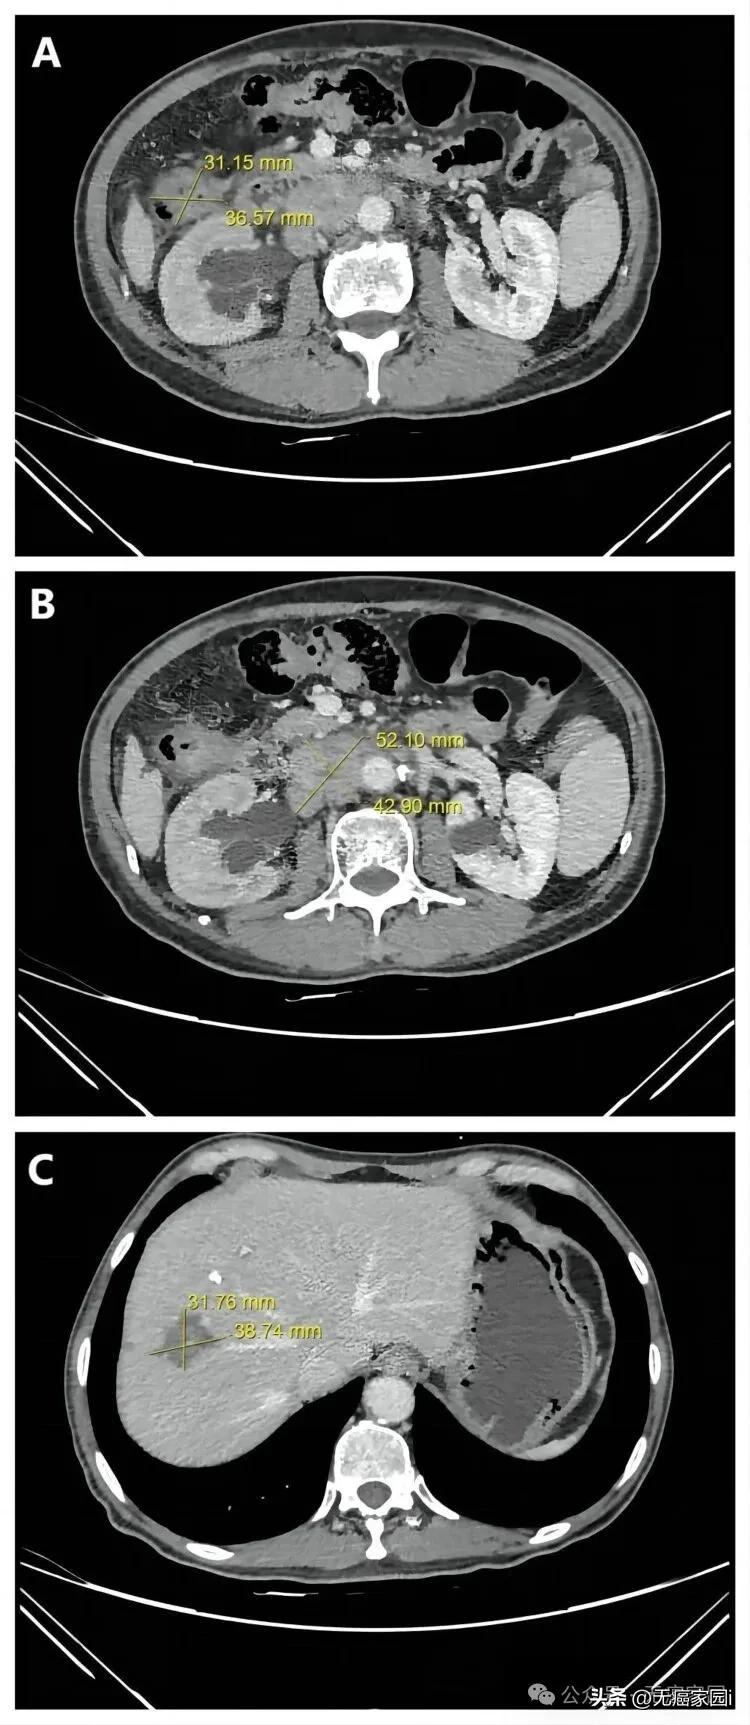

患者第一、二、三次治疗后腹部轴位 CT 图像,显示病灶大小。

A. 结肠肿瘤;B. 淋巴结转移病变;C. 肝转移;CT:计算机断层扫描。

肿瘤大幅缩小:影像学检查显示,结肠原发肿瘤和肝脏转移灶均明显缩小,病情达到部分缓解(PR)。最终,肿瘤缩小至可以进行根治性手术的范围,并实现了病理完全缓解(pCR),即在手术切除的标本中已找不到存活的癌细胞。